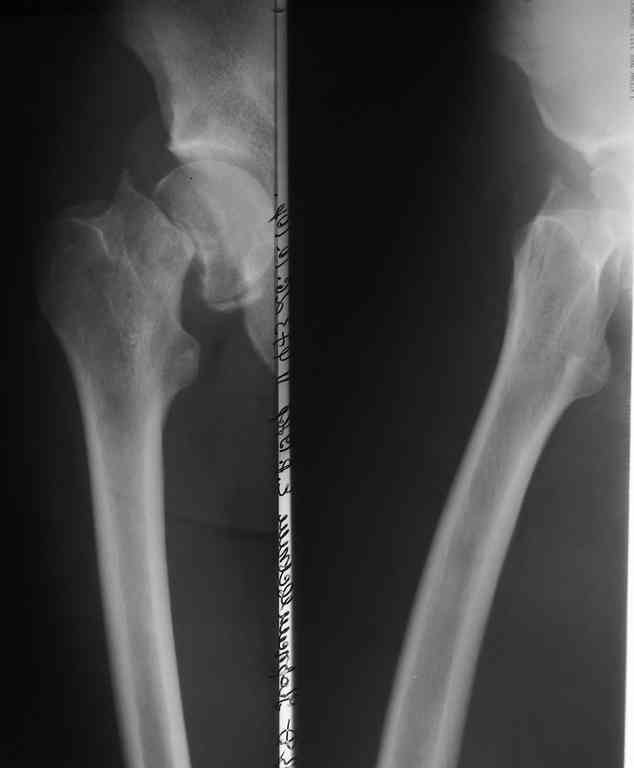

Рентгенография

Если решитесь делать остеосинтез, покажите результат обязательно. Все-таки субкапитальный перелом с вероятным переходом на головку, почти через 3 месяца после травмы. Возможность закрытой репозиции через такой срок вызывает сомнения. Открытая еще больше нарушит кровоснабжение. КТ до операции было бы неплохо сделать.

Вы действительно считаете возможным закрытую репозицию субкапительного garden 4 перелома через 3 месяца после травмы? Если "да" - на каком основании? имеется собственный опыт удачных репозиций или данные литературы? если литературы - какой?

Независимо от метода фиксации, любой перелом шейки бедра может осложниться ложным суставом. Часто у молодых, после травмы с высокой энергией и особенно с вертикальными переломами. Более половина леченных после переломов по Pauwels III заканчиваются аваскулярным некрозом или ложными суставами.

Молодой возраст больного является противопоказанием к артропластике, и необходимо сделать все возможное, чтобы уйти от "внутренней ампутации" головки. С момента травмы более трех месяцев, и жизнеспособность головки пока не вызывает опасений. Свободная подвиженность по линии перелома доказывает, что патология в стадии ложного сустава.